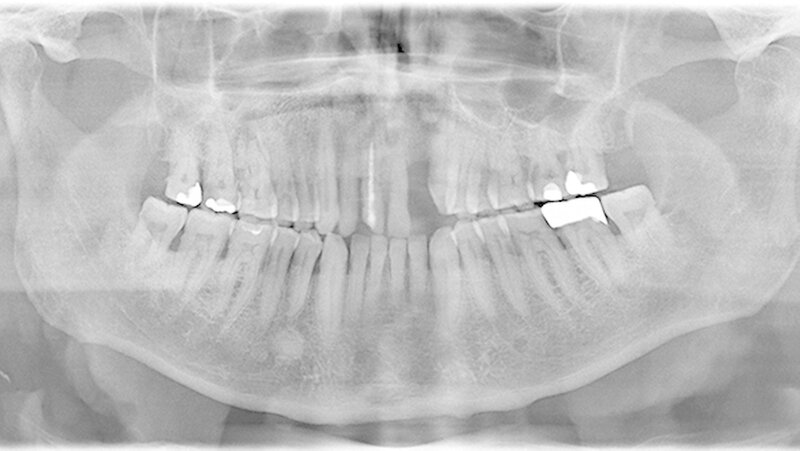

Ein 80 Jahre alter Patient stellt sich im September 2016 in der Poliklinik mit der Bitte um festsitzende Versorgung der Frontzahnlücke in Regio 22 vor (Abbildungen 1 und 2) Der Zahn 22 musste vor etwa einem Jahr parodontal bedingt extrahiert werden. Seitdem war diese Lücke durch einen Interimsersatz versorgt. Nach klinischer und röntgenologischer Befundung stellt sich schnell die Problematik dar, die im Rahmen der Versorgung dieser Frontzahnlücke auftreten wird.

Weiterhin werden eine Therapie-bedürftige Karies an 17 und ein apikal beherdeter 16 diagnostiziert, deren Behandlung ebenfalls durchgeführt wird.

Die Versorgung der Frontzahnlücke in Regio 22 wird intensiv mit dem Patienten diskutiert. Aufgrund des absoluten Mangels an ortsständigem Knochen, des hohen Patientenalters sowie der eher mäßigen Mundhygiene scheidet eine Implantation mit Knochenaugmentation aus. Hinzu tritt die starke, vor allem im Frontzahngebiet ausgeprägte Parodontitis. Ein langfristiger Erhalt des endodontisch versorgten 11 sowie des stark parodontal kompromittierten 21 erscheint unrealistisch.

Für eine konventionelle brückenprothetische Versorgung scheiden die Schneidezähne ebenfalls aus: Zum langfristig prognostisch sicheren Ersatz des 22 wären Extraktionen und mehrere Substanz-opfernde Präparationen unausweichlich. Aufgrund des hohen Patientenalters und des Ausscheidens klassischer prothetischer Rehabilitationsmaßnahmen wird die Frontzahnlücke mit einer Adhäsivbrücke aus Metallkeramik versorgt (Abbildungen 3 und 4).